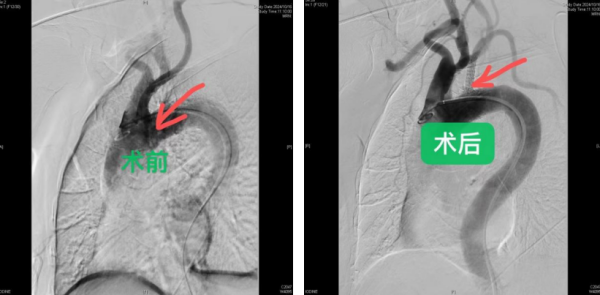

“患者在心血管内科接受了颈动脉与锁骨下动脉的彩超检查,检查结果明确显示其左锁骨下动脉存在闭塞现象,并伴随有左锁骨下动脉盗血综合征。基于这一诊断结果,经过多学科会诊,患者被转至外周血管介入科进一步治疗。”赵扬程介绍。随后,赵扬程主任及其团队对患者的病情进行了全面评估,并决定采用介入手术进行治疗。在DSA数字减影血管造影下,医生成功将导丝通过患者左锁骨下动脉的闭塞段,并实施了球囊扩张和覆膜支架植入手术,成功开通了闭塞的左锁骨下动脉。

图片说明:术前:左锁骨下动脉未见显影,延迟造影见左锁骨下动脉经左椎动脉供血,也就是“盗血”;术后:左锁骨下动脉闭塞段经过球囊扩张及支架植入,可以看到左锁骨下动脉造影良好,血流通畅。